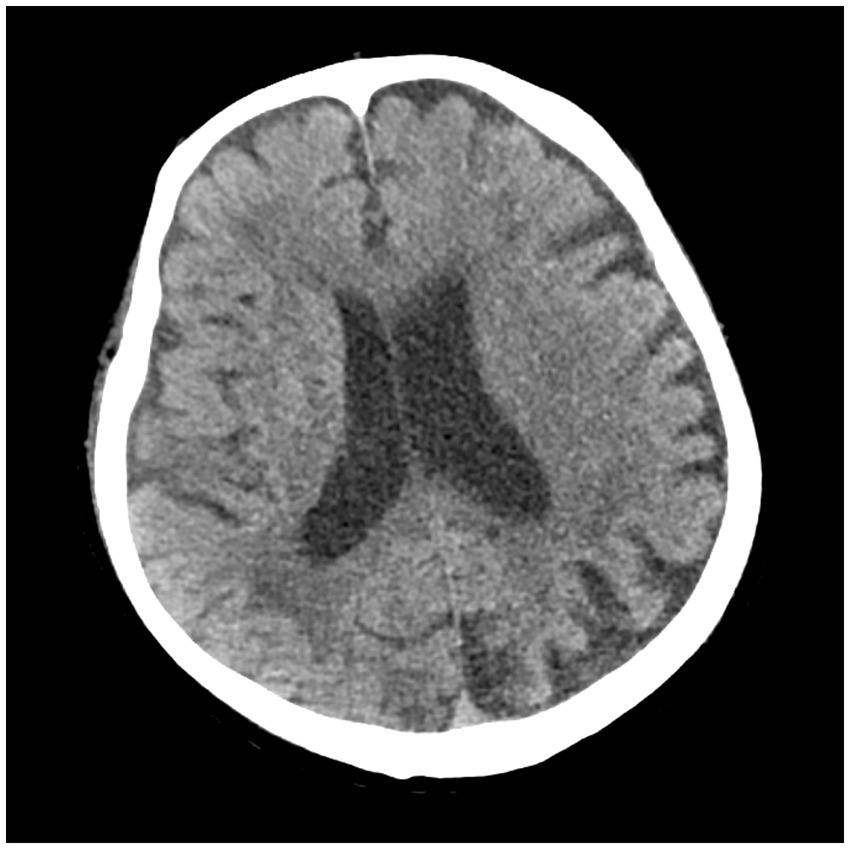

After admission, he received treatment, including rehydration, vasopressor (metaraminol bitartrate), antibiotics (imipenem-cilastatin sodium and moxifloxacin), prednisone (5 mg qd), and other support treatment. Pathogens were negative after 7 days of blood culture. On day 7 of treatment, the patient had a sudden convulsion with repetitive jerks, loss of consciousness, and eyes gazing to the right. A measure of 3 mg midazolam was injected to control symptoms, and cranial CT (Figure 3) was performed again, which revealed multiple low-density regions of both the cerebral and cerebellar hemispheres. Patent foramen ovale (PFO) was negative on transthoracic and contrast echocardiography, but it showed 0.7 cm*0.6 cm vegetation on the mitral valves (Figure 4, white arrow). Up to this point, infectious endocarditis was diagnosed.

Figure 3

Repeated cranial CT of the patient.